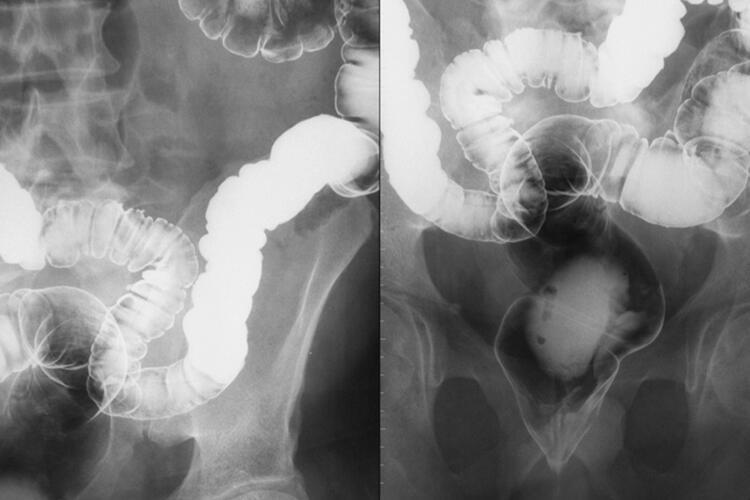

Günümüzde başta kolonoskopi olmak üzere endoskopik yöntemlerle İBH tanısı koymak oldukça kolaydır. Kan ve gaita tahlilleri yanı sıra bilgisayarlı tomografi gibi görüntüme yöntemleri de hastalık tanısı, ayırıcı tanısı ve tedaviye yanıtın ölçülmesi için yardımcı yöntemlerdir.